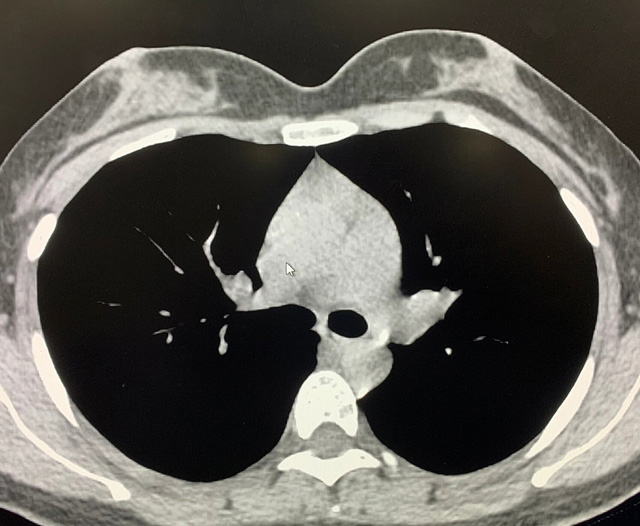

能譜純化技術的核心是通過物理濾過(如錫濾片)或軟件算法,選擇性濾除低能X射線光子,保留高能光子。在胸部低劑量CT掃描中顯著提升了圖像質量與輻射劑量的平衡。

優勢輻射劑量顯著降低相較於常規CT,輻射劑量減少約70%-90%,尤其適合需多次隨訪的高危人群(如肺癌篩查),降低輻射相關癌症風險早期肺癌篩查效果明確可清晰檢測毫米級肺結節,顯著提高早期肺癌檢出率,降低死亡率。檢查快捷且普及性高單次掃描僅需數秒,無需對比劑,設備廣泛配置於基層醫院,便於大規模篩查。長期成本效益顯著雖單次費用與常規CT相近,但早期幹預可大幅降低晚期治療費用及社會醫療負擔。技術優化提升圖像質量迭代重建算法(如ASIR、MBIR)在降低劑量同時減少噪聲,平衡影像質量與安全性。